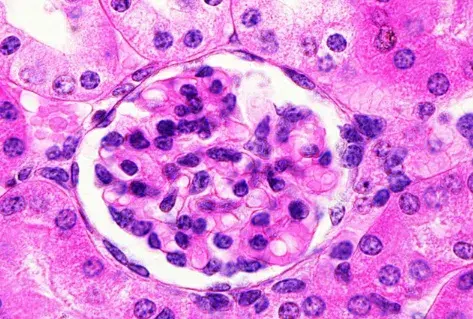

É possível identificar um glomérulo com quebra ruptura da MBG, com crescente celular no espaço de Bowman (seta branca), célula gigante multinucleada (estrela) e ruptura da cápsula de Bowman (seta preta) (PAS; 400×). PAS, ácido periódico-Schiff.

A biópsia renal revelou GN crescêntica necrotizante difusa sem hipercelularidade endocapilar. Alguns raros glomérulos continham células gigantes multinucleadas.

A avaliação da microscopia de luz pode ajudar na diferenciação de casos de **GN por anti-MBG** de casos **GN-ANCA**, já que na GN anti-MBG não observamos hipercelularidade endocapilar e pode ser identificado a presença de células gigantes multinucleadas, estas células gigantes multinucleadas resultam a natureza explosiva e a rápida destruição dos glomérulos observadas em anti-MBG

Desta forma, a presença de lesões crescentes temporalmente semelhantes e células gigantes multinucleadas na microscopia de luz (MO) pode ajudar no diagnóstico precoce.